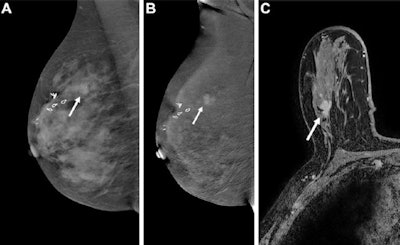

A team led by Marissa Lawson, MD, from the University of Washington in Seattle found that abbreviated breast MRI had comparable performance to standard MRI. Meanwhile, CEM had lower recall and higher specificity compared to both MRI methods but also had lower cancer detection rate and sensitivity.

The researchers found that while abbreviated MRI showed no significant differences in performance metrics with standard MRI, CEM varied in performance.

Additionally, the authors wrote that while their meta-analyses did not report lesion characteristics, these may have impacted CEM's sensitivity in their study. They called for future studies with larger sample sizes to investigate CEM's tradeoffs, as well as patient acceptance.

"In addition, our MRI protocol has spatial resolution that exceeds [ACR] accreditation standards, which likely facilitates superior depiction of lesions compared with CEM," the authors wrote.